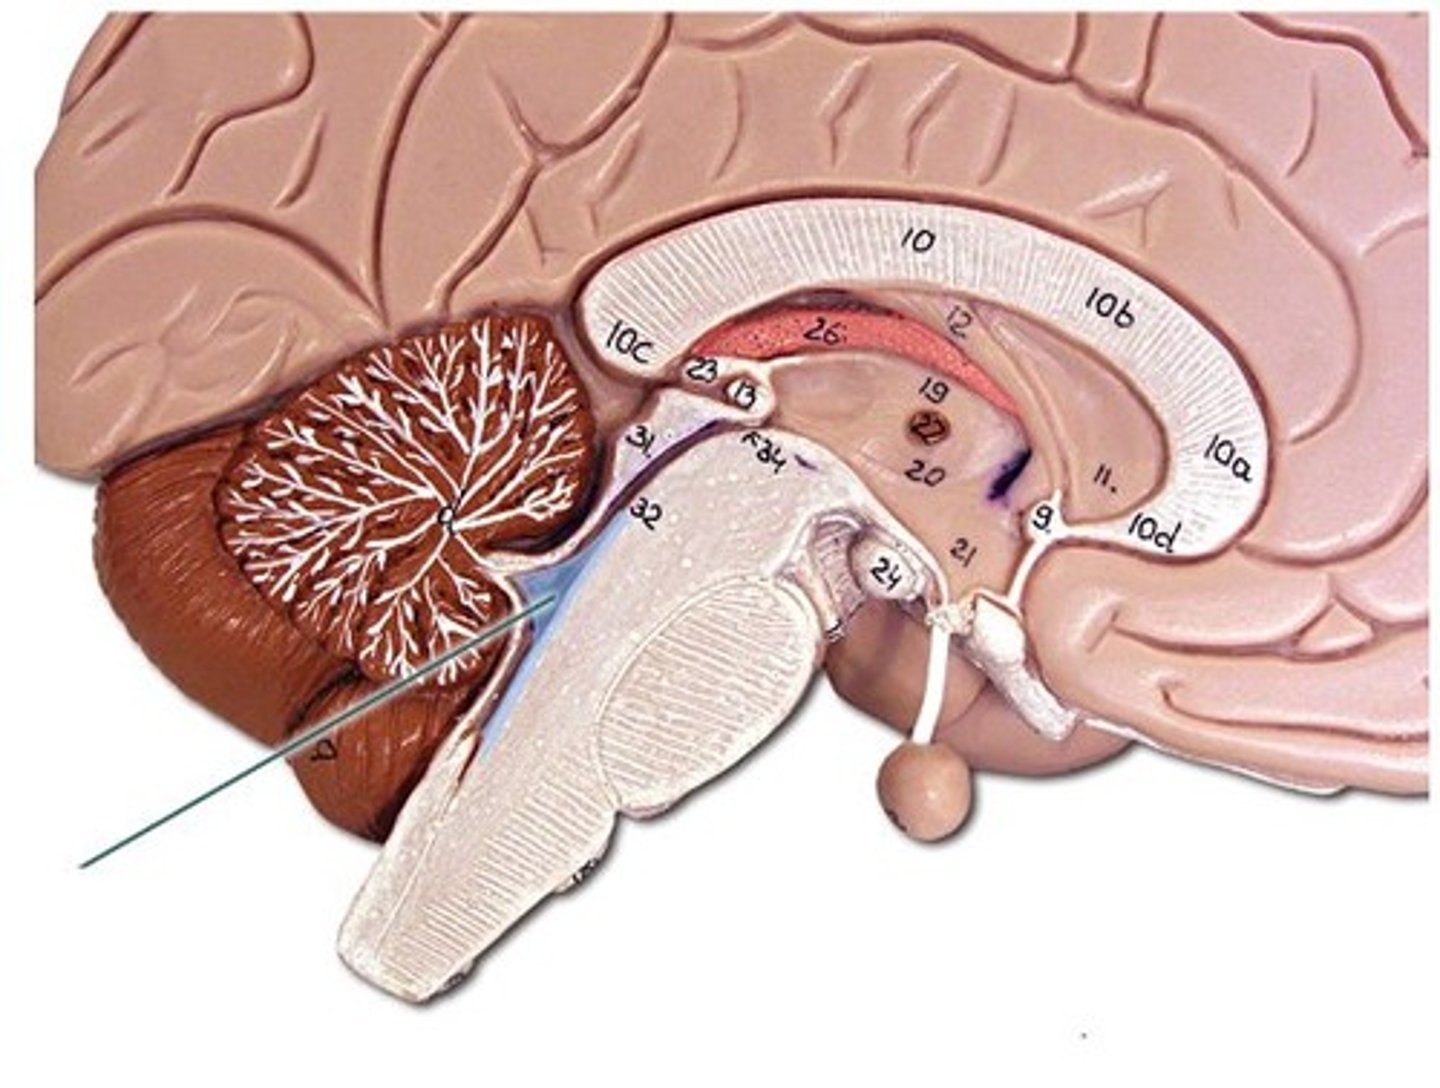

medulla oblongata

basic life support, heart beating, etc.

decussation of pyramids

where the cleavage furrow becomes almost flat - the reason for contralateral control

pons

control of breathing

midbrain

immediate reflexes

cerebral peduncles

connect lower and upper brain, cerebrum to brainstem

corpora quadrigemina

located in the midbrain; contains reflex centers for vision and auditory reflexes.

superior colliculi

part of corpora quadrigemina, visual reflexes

inferior colliculi

part of corpora quadrigemina, auditory reflexes

diencephalon

thalamus and hypothalamus

cerebellum

balance, equilibrium, gross motor movement

vermis (cerebellum)

The tissue between the two cerebellar hemispheres

arbor vitae